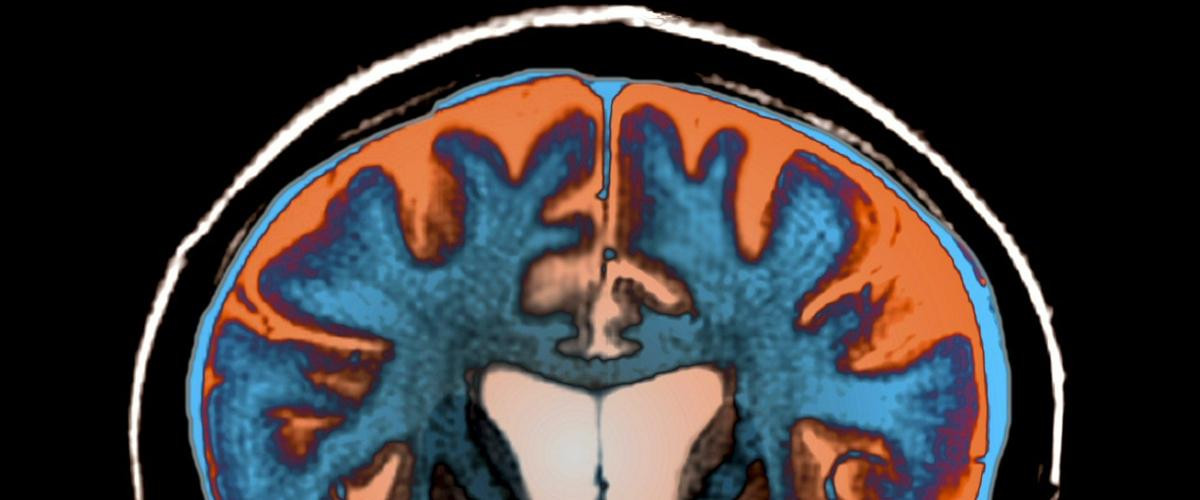

Выводы указывают, что сокращение теломер может стать биомаркером для диагностики и мониторинга развития болезни Хантингтона. Пока заболевание неизлечимо, проявляется у людей среднего и пожилого возраста, влияет на психическое здоровье, когнитивные и моторные функции.